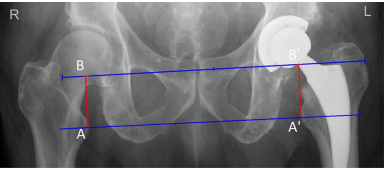

下肢长度差异 (Leg length discrepancy)

下肢长度差异是THR术后最常见的并发症之一。肢体延长比缩短更常见,并且患者更容易察觉。根据研究,当手术肢体延长超过6 mm或缩短超过10 mm时,患者会感知到下肢长度差异。然而,最大的问题是超过10 mm的不等长,因为它们影响日常功能。它们可能导致步态异常、不稳、坐骨神经痛和背痛。此外,延长超过10 mm还会伴随其他并发症:跛行、骨盆倾斜和幻灭感。

在前后位X线片上,下肢长度差异表示为穿过双侧泪滴点下缘的直线到相应小转子尖 (tip of the lesser trochanter) 的垂直距离之差。

下肢长度差异测量。A 和 A' 位于小转子尖水平。 B 和 B' 位于泪滴点下缘水平。 AB 和 A'B' 线是穿过泪滴点下缘的直线到相应小转子尖的距离。 AB 与 A'B' 长度之差即为下肢长度差异。